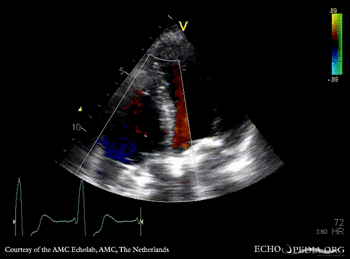

Four prosthetic valves

PLAX: mitral valve prosthesis and aortic valve prosthesis PLAX with Color Doppler